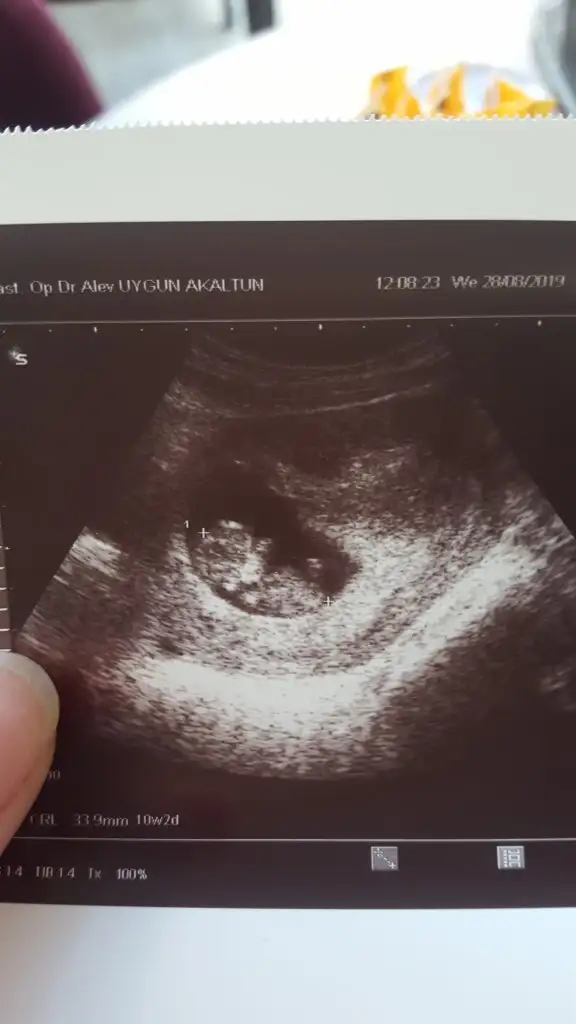

Nub o kadar paralelki kız sandık paşanı 3 kişi yanılmışız meltem kafa şekline bilmiş saglıkla gelsin

Ben hep soyluyorum usg ye gore yorum yapiyoruz ultrasonla birebir bakmiyoruz o usg deki nub 10 kiside olsa 9 u kiz dir kesin iste bir tane istisna cikmis hayirlisi olsun diyorum

Aynen o kişi de benim işteBen hep soyluyorum usg ye gore yorum yapiyoruz ultrasonla birebir bakmiyoruz o usg deki nub 10 kiside olsa 9 u kiz dir kesin iste bir tane istisna cikmis hayirlisi olsun diyorum

Aynen sağlıklı hayırlı olsun inşallah, bende kız isteyince 1 kişi yanılmıştır demiştim kendi kendimeNub o kadar paralelki kız sandık paşanı 3 kişi yanılmışız meltem kafa şekline bilmiş saglıkla gelsin

Nub görünmüyor başka varmı renksiz usgBana şu fotoya göre bi tahmin yaparmısınız ya

Nub görünmüyor başka varmı renksiz usg

Net olmamakla birlikte Kız gibi tam net degil başka usg varmıKızlar bu da arkadaşıma ait bi görüntü. 10+2. Tahminlerinizi merak ediyoruz

Bi tane daha var ama onda hiç belli değil en belirgin olanı buNet olmamakla birlikte Kız gibi tam net degil başka usg varmı